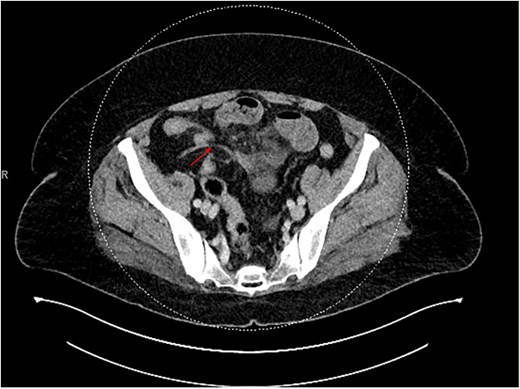

Contrast-enhanced CT of the abdomen and pelvis showed two closely positioned transition points in the right lower quadrant with moderate mesenteric congestion and interloop fluid. Those findings were suggestive of a closed-loop SBO (Fig. 1). The appendix was noted to be unremarkable in caliber but mildly stretched toward the transition point (Fig. 2). An enlarged paraesophageal hernia was also identified.

CT showing closed bowel loop obstruction and two closely positioned transition points.